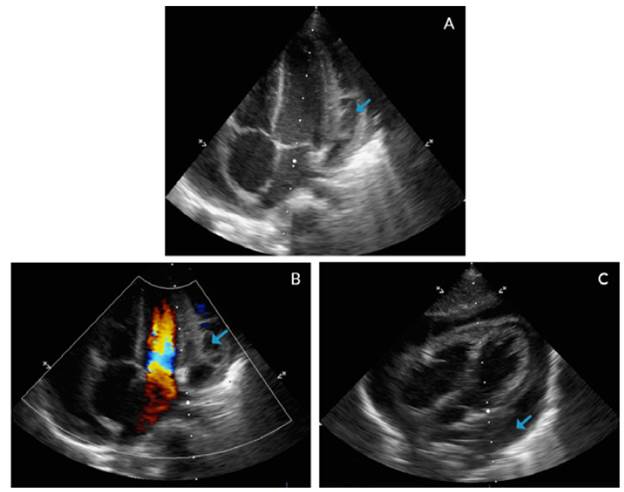

In addition, an echocardiogram showed global pericardial effusion and the presence of thick membranes between the visceral and parietal pericardium, without signs of cardiac tamponade, adequate ventricular function, ventricular ejection fraction of 77% and central venous pressure of 8-10mmHg, without signs of pulmonary hypertension (Figure 3).

Echocardiogram with apical four chamber view (A, B) and coronal axial plane (C).

Figure 3: Echocardiogram with apical four chamber view (A, B) and coronal axial plane (C).

Source: Own elaboration based on the data obtained in the study.

Studies to rule out immunological involvement were within normal limits (Table 1). Given the cyclic and echocardiographic improvement, discharge was authorized (Figure 4).

Echocardiogram taken before discharge.

Figure 4: Echocardiogram taken before discharge.

The echocardiogram is the diagnostic method of choice to clarify radiological findings. 2,3 In this case, it showed a global pericardial effusion associated with the presence of thick membranes between the visceral and parietal pericardium, without cardiac tamponade, systolic-diastolic function involvement or alterations in the myocardium. Computed tomography (CT) is indicated when emergency echocardiogram is not available and when inconclusive echocardiographic results, poor response to treatment, atypical presentation, penetrating lesion, suspicion of neoplasms and pulmonary infections or mediastinitis are observed. 13 This patient did not require chest CT because of his rapid improvement, which reduced the possibility of complications.